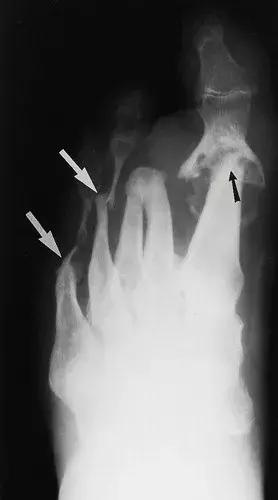

图21:42岁糖尿病女性,前足的神经性骨关节病。X线片显示 萎缩的变化导致了“尖头骨”(白色箭头)。第一跖趾关节具有研杵形态(黑色箭头)。 前脚的萎缩性神经性骨关节病。